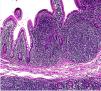

Dentro de las características histopatológicas de los tumores, los linfomas identificados en esta serie de casos se caracterizaron por una proliferación de linfocitos pequeños y hendidos en una disposición nodular en la submucosa o en la mucosa de los segmentos afectados (fig. 11). Citológicamente demostraron un núcleo hipercromático, pequeño (7μm de diámetro) y hendido, con escaso citoplasma (fig. 12). En todos los casos se llevó a cabo una batería de inmunohistoquímica para confirmar el diagnóstico, donde destacó la positividad en membrana citoplásmica para CD20 y CD5 en los linfocitos B neoplásicos (fig. 13a,b) y para ciclina D1 en el núcleo de los linfocitos neoplásicos (fig. 13c), hallazgos que son confirmatorios del diagnóstico. En la mucosa adyacente de los tumores se identificaron solamente atrofia del epitelio y edema. No se observó linfocitosis intraepitelial ni microorganismos patógenos; en las biopsias gástricas no se identificó la presencia de Helicobacter pylori.